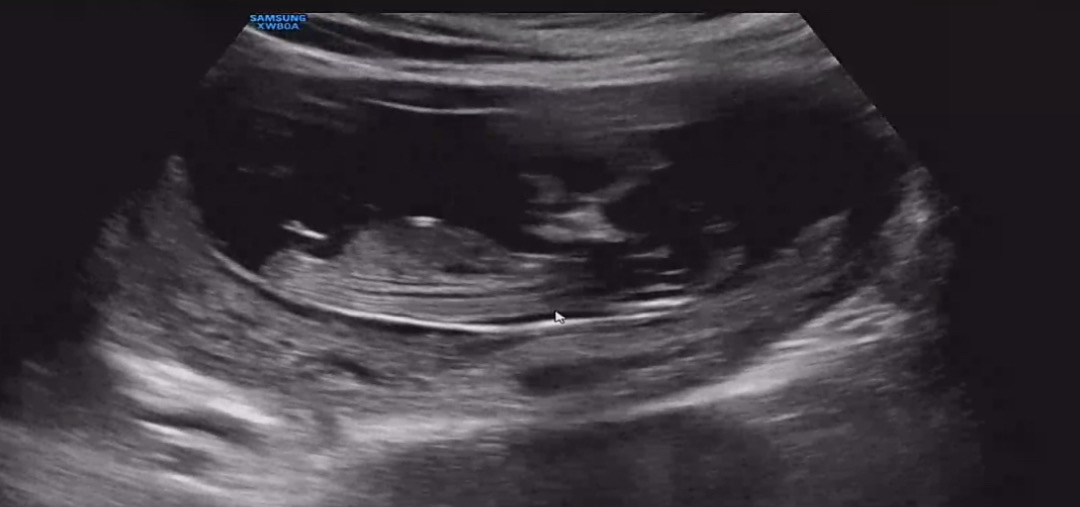

11주랑 12주 사이 초음파 성별 보이시나요

성별이 지금 보이나여??? 너무 궁금해요 ㅋㅋㅋ

공주님 같아요 ㅎ